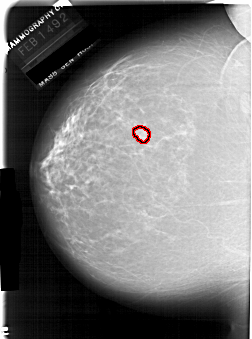

FILE: A_1940_1.LEFT_MLO.OVERLAY

TOTAL_ABNORMALITIES 1

ABNORMALITY 1

LESION_TYPE MASS SHAPE LOBULATED MARGINS CIRCUMSCRIBED

ASSESSMENT 3

SUBTLETY 4

PATHOLOGY BENIGN

TOTAL_OUTLINES 1

BOUNDARY